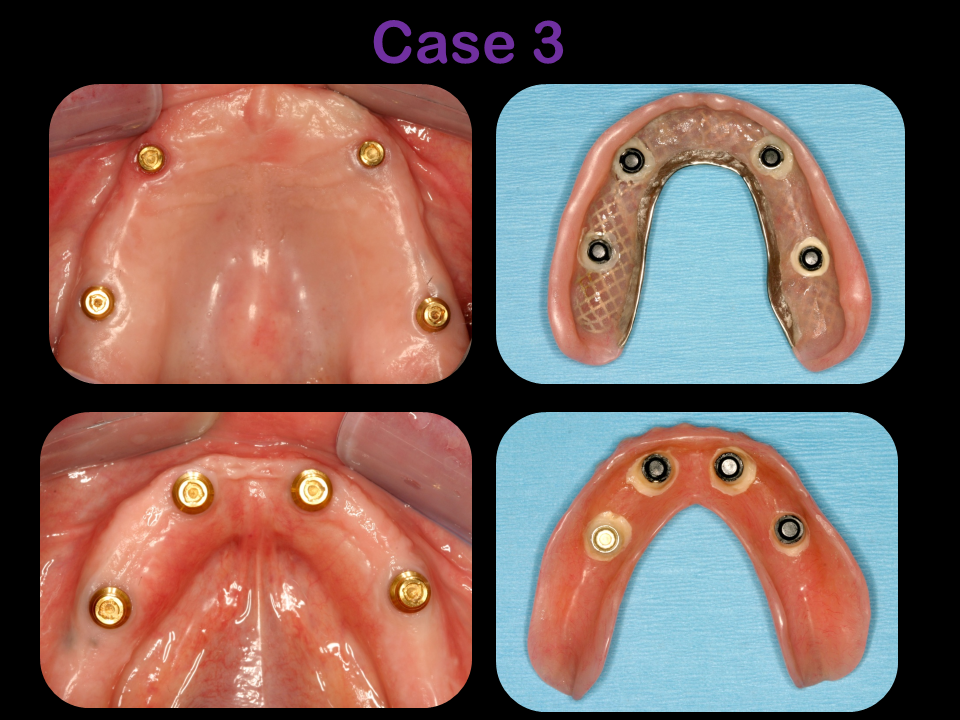

Explore the artistry and precision of Dr. Feldner’s 32 years of expertise through our photo gallery, showcasing the remarkable transformations in periodontics, implantology, and bone grafting. Each before-and-after photo is a testament to Dr. Feldner’s commitment to excellence, reflecting a mastery that blends innovative techniques with a passion for restoring smiles and health.